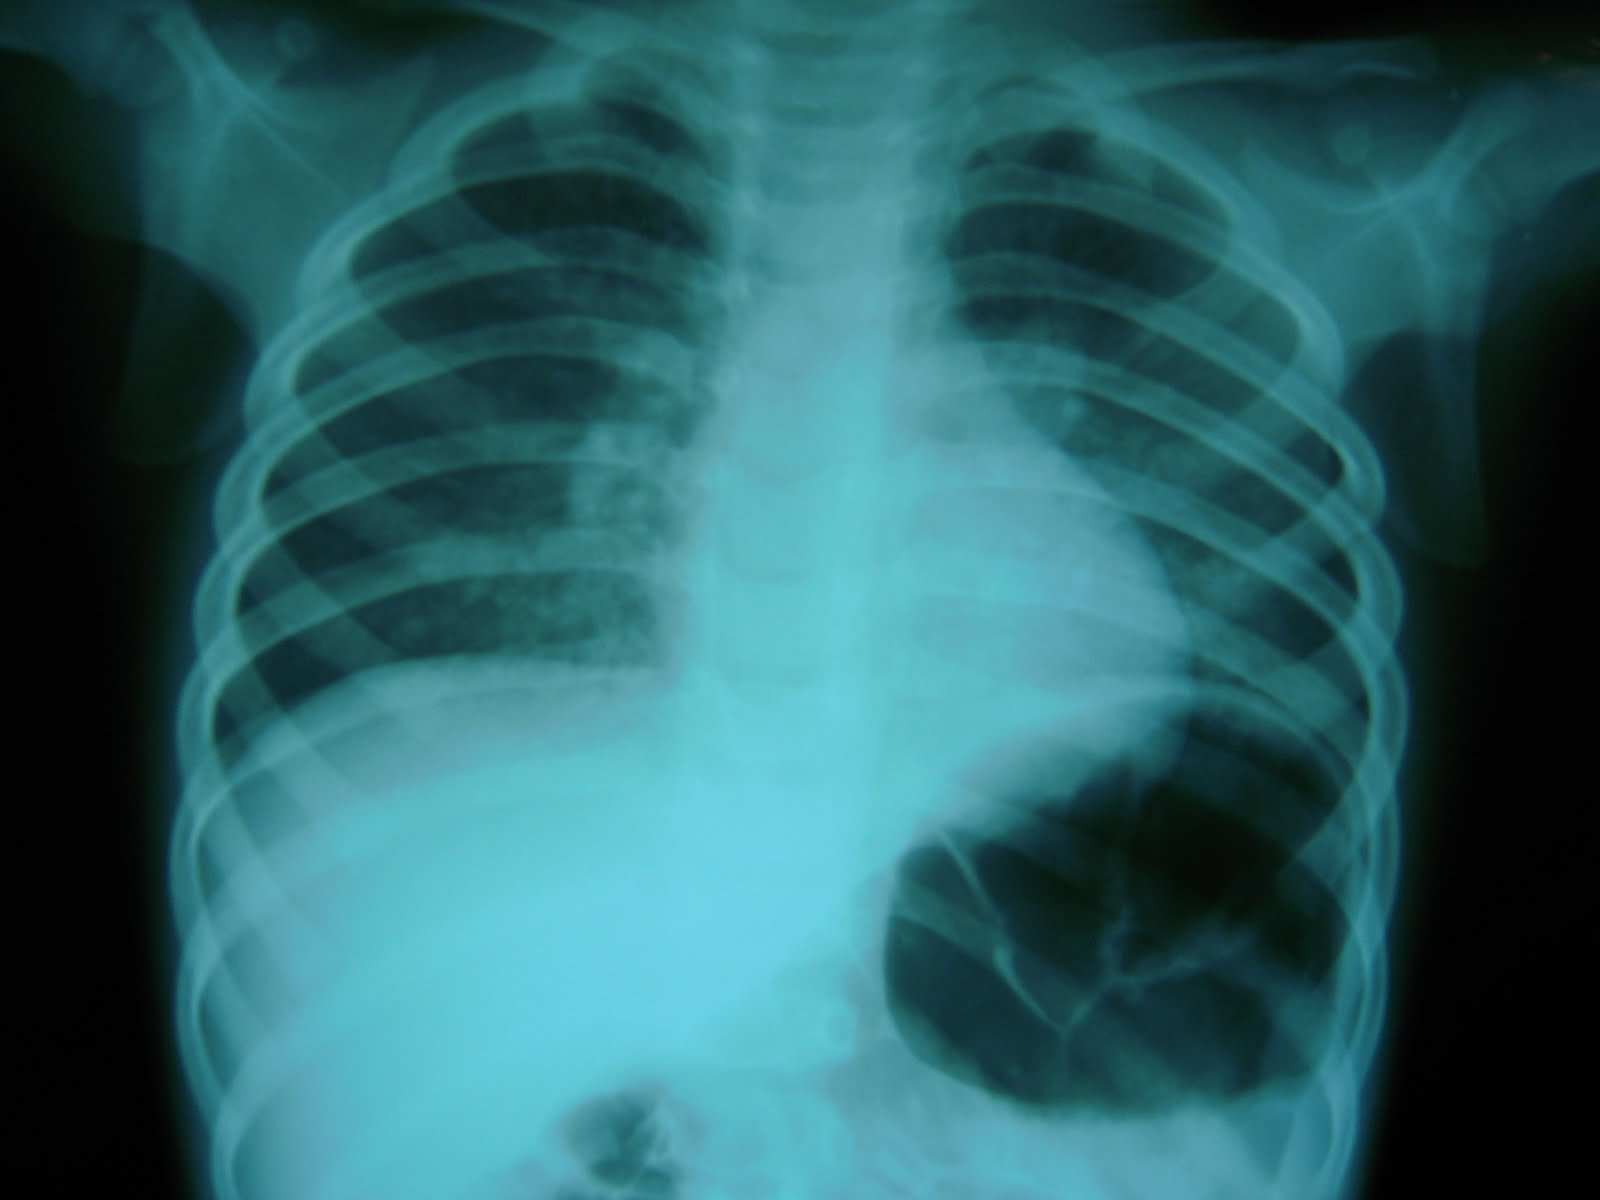

図1.マイコプラズマ肺炎の年別・週別発生状況(2001~2011年第43週)

レジデントノート 2017年1月号掲載【解答・解説】抗菌薬無効の肺炎として紹介された20歳代女性

マイコプラズマ肺炎(小児)患者の看護(症状・看護計画・注意点)について

今日なに読もう〜病院総合診療医の論文ブログ〜マイコプラズマ肺炎の画像所見コメント